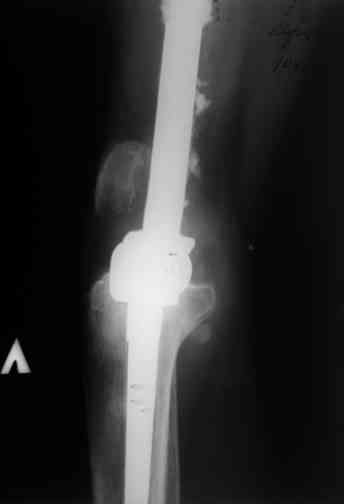

Через 3 года после травмы констатировало отсутствие консолидации бедренной кости, сохранение признаков хронического остеомиелита (свищ в нижней трети левого бедра). Произведен демонтаж аппарата, реостеосинтез бедренной кости спице-стержневым аппаратом, некрсеквестрэктомия. В аппарате удалось лишь частично произвестиустранение углообразной деформации бедренной кости [image 05] .

Через 4,5 лет после травмы выявлены рентгенологические признаки консолидации перелома, признаки хронического остеомиелита купировались. Аппарат был демонтирован. Пациент продолжил ходьбу с дозированной нагрузкой на конечность при помощи костылей. Через 2 месяца начал ходить при помощи трости. Однако, еще через 2 месяца отметил появление свищей на бедре с гнойным отделяемым и укорочение длины конечности. При осмотре в январе 2007 г.: пациент ходит при помощи костылей без опоры на левую нижнюю конечность, на бедре имеются множественные рубцы, на наружной поверхности сегмента в верхней и нижней третях имеются два свищевых хода со скудным серозно-гнойным отделяемым; отечности тканей конечности нет, пальпация безболезненная, отмечается укорочение длины конечности на 5 см, патологическая подвижность не определяется, имеется стойкая разгибательная контрактура коленного сустава (разгибание - 180 гр, сгибание - 170 гр), признаков нарушения кровоснабжения и иннервации тканей конечности нет. Температура тела нормальная. В общих анализах крови и мочи отклонений от нормы нет. [image 06,07, 08 (стрелками отмечены свищевые раны, 09, 10]Дорогие коллеги, я уверен, что у многих из вас после знакомства с данным клиническим наблюдением появится множество вопросов, касающихся уже проведенного лечения (особенно, сроков и способов). Сразу оговорюсь - я не смогу правильно ответить на многие вопросы (особенно касающиеся предшествующего периода лечения). Прошу вас, конечно по возможности, сосредоточить внимание не на разборе допущенных ошибок (проведенного лечения), а помочь добрым советом относительно тактики наших дальнейших действий. Наверное, кто-то располагает бесценным опытом лечения подобной патологии.